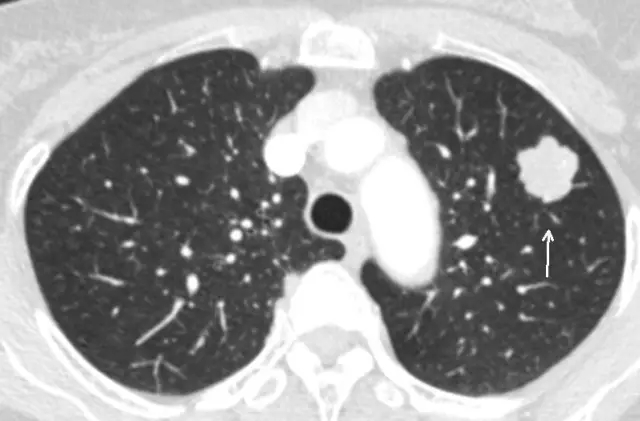

是指肺內(nèi)直徑≤3cm的密度增高影,通俗講就是CT上黑色的肺里有小白點(diǎn)。>3cm的白色塊狀影稱為肺腫塊,通常腫瘤的可能性很大。

結(jié)節(jié)直徑≤3cm

結(jié)節(jié)直徑>3cm